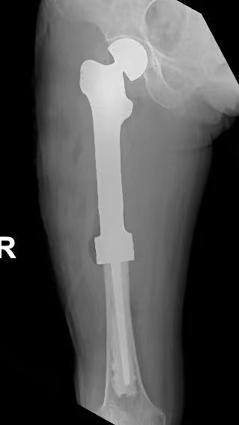

患者术后没有任何不适,恢复良好,未输血。术后拍片显示3D打印假体按计划植入,髋臼匹配良好。术后3天患者可坐起,术后1周患者可下地行走功能锻炼,术后2周可基本自主扶拐活动。2周间断拆线后出院。

恶性骨肿瘤的手术及关节重建是骨科手术的难点和雷区,3D打印定制假体治疗一般都是国内著名三甲医院骨肿瘤科开展,花费也比较贵。借助3D打印,以及邢科主任较早对此领域积累的技术力量,该院骨外科三病区让患者两次住院花费合计不到5万元即完成了这种个性化设计和治疗。过去对于普通家庭遥不可及的新科技治疗手段,在该院和科室的共同努力下正在让越来越多的群众受益。